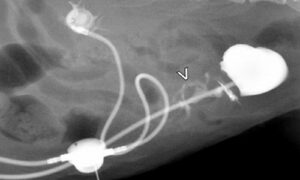

Prospective evaluation of an extra-anatomic ureteric bypass device for management of cats with ureteric obstruction by Zoe Halfacree and colleagues at the RVC

Use of a subcutaneous ureteral bypass (SUB) to overcome ureteral obstructions in cats was found to be associated with a high prevalence of complications but a median survival time exceeding 2 years. Ultrasonography was useful in the initial assessment of SUB usage and fluoroscopy was essential in identifying leaks, blockages or SUB displacement, and for guiding surgical treatment.Ureteral obstructions are becoming increasingly diagnosed in cats, and are commonly caused by calcium oxalate kidney stones. An SUB consisiting of an extra‐anatomic device consisting of a locking loop nephrostomy catheter connected to a cystostomy catheter via a subcutaneous port was retrospectively assessed in cats treated for benign ureteral obstruction.